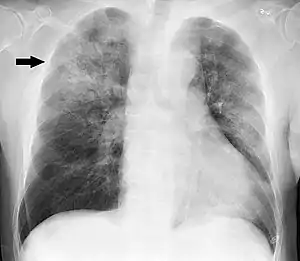

Clinical features may include initial symptoms of an upper respiratory tract infection mimicking a viral infection, usually associated with fevers, often low-grade. This may progress to the lower respiratory tract in a few days, with features often resembling those of a wheezy bronchitis. Sputum may be difficult to expectorate and is often grey or creamy in color. The cough may persist for weeks without appropriate treatment. Many cases are diagnosed after presenting chest infections that do not respond to penicillins or first-generation cephalosporins. A chest X-ray can identify alveolar consolidation.[7]